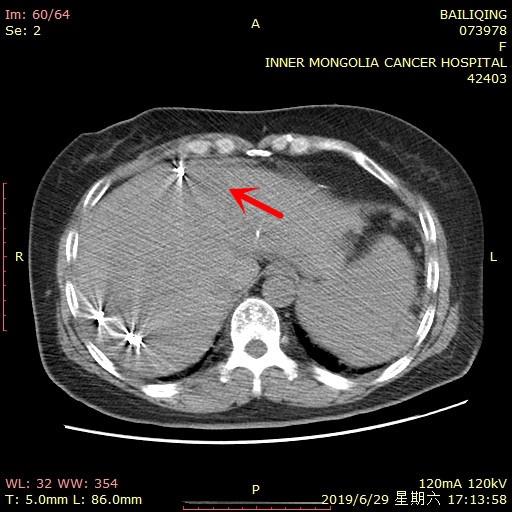

病例一:患者白某,女,52岁,肺癌患者肝脏转移瘤行微波消融手术。转移瘤病灶大小约1.5cmx2cm,病灶位于肝左叶肋软骨后缘1cm处,同时离膈肌位置较近,进针角度复杂,需要避开肋软骨及膈肌层面。通过导航机器人计划系统设计出由外侧向内侧的进针路径,进针角度-55°,进针深度8cm,实现一次计划同时布置3针。通过扫描验证,实现一次进针到达理想消融位置,消融完全。手术过程中CT扫描共三次,计划处置时间10min,术后未发生并发症。